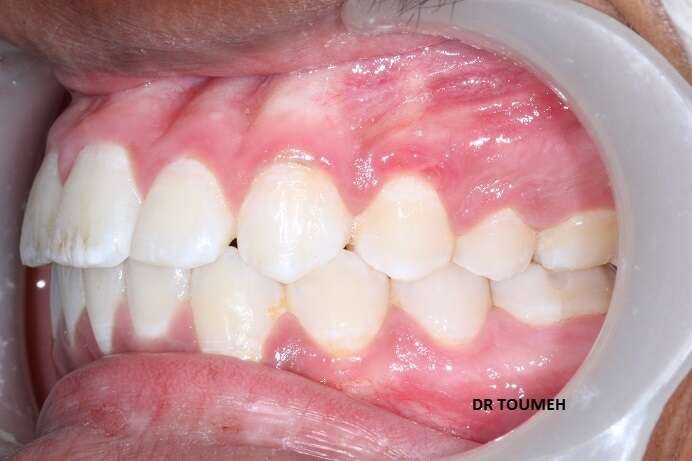

Avant

Après